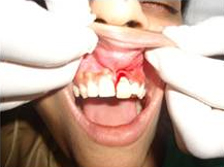

Pre Operation

Single Tooth Implant

Placement of Bone Grafting

Use of Bone Graft & GTR membrane for an Implant